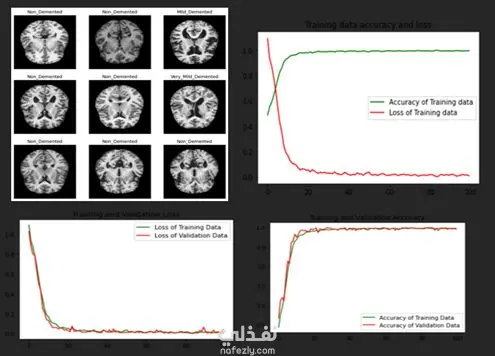

يهدف المشروع إلى تحليل التآثرات الجينية (Epistasis) للكشف عن التفاعلات بين الجينات المرتبطة بمرض ألزهايمر، وذلك باستخدام تقنيات تعلم الآلة وطرق التحليل الإحصائي. يشمل العمل: جمع البيانات الجينية ومعالجتها. تطبيق خوارزميات تعلم الآلة لاكتشاف العلاقات المخفية بين الجينات. تحليل التآثرات (Epistasis) لفهم كيفية تأثير مجموعات الجينات معًا على قابلية الإصابة بالمرض. استخدام تقنيات التعلم الجماعي (Ensemble Learning) لتحسين دقة النتائج. عرض النتائج من خلال تقارير ورسوم بيانية توضح أهم التفاعلات الجينية المكتشفة. هدف المشروع هو المساهمة في فهم الأسس الجينية لمرض ألزهايمر، مما يساعد الباحثين والأطباء في تطوير استراتيجيات أفضل للتشخيص المبكر والعلاج المستقبلي.